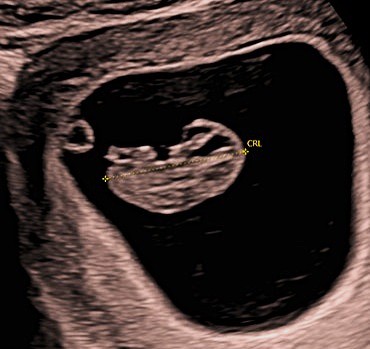

• From around 6½–7 weeks onwards, a fetal pole is usually visible and a heartbeat can typically be detected.

• Between 7 and 10 weeks, the scan provides more definitive reassurance. A heartbeat should be clearly seen, early development can be assessed, and the number of babies can be confirmed.

The scan is usually performed initially through the abdomen. In very early pregnancy, or if views are limited, an internal (transvaginal) scan may be recommended to obtain clearer images. This is a safe and commonly used technique and will only be performed with your understanding and consent.